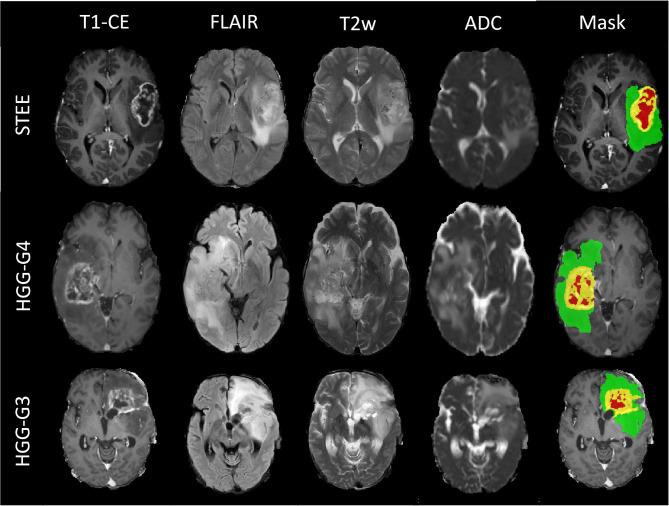

To build a machine learning-based diagnostic model that can accurately distinguish adult supratentorial extraventricular ependymoma (STEE) from similarly appearing high-grade gliomas (HGG) using quantitative radiomic signatures from a multi-parametric MRI framework. We computed radiomic features on the preprocessed and segmented tumor masks from a pre-operative multimodal MRI dataset [contrast-enhanced T1 (T1ce), T2, fluid-attenuated inversion recovery (FLAIR), apparent diffusion coefficient (ADC)] from STEE ( = 15), HGG-Grade IV (HGG-G4) ( = 24), and HGG-Grade III (HGG-G3) ( = 36) patients, followed by an optimum two-stage feature selection and multiclass classification. Performance of multiple classifiers were evaluated on both unimodal and multimodal feature sets and most discriminative radiomic features involved in classification of STEE from HGG subtypes were obtained. Multimodal features demonstrated higher classification performance over unimodal feature set in discriminating STEE and HGG subtypes with an accuracy of 68% on test data and above 80% on cross validation, along with an overall above 90% specificity. Among unimodal feature sets, those extracted from FLAIR demonstrated high classification performance in delineating all three tumor groups. Texture-based radiomic features particularly from FLAIR were most important in discriminating STEE from HGG-G4, whereas first-order features from T2 and ADC consistently ranked higher in differentiating multiple tumor groups. This study illustrates the utility of radiomics-based multimodal MRI framework in accurately discriminating similarly appearing adult STEE from HGG subtypes. Radiomic features from multiple MRI modalities could capture intricate and complementary information for a robust and highly accurate multiclass tumor classification.

构建一个基于机器学习的诊断模型,该模型能够使用多参数MRI框架中的定量放射组学特征,准确区分成人幕上脑室外室管膜瘤(STEE)与外观相似的高级别胶质瘤(HGG)。我们从STEE(n = 15)、IV级HGG(HGG-G4)(n = 24)和III级HGG(HGG-G3)(n = 36)患者的术前多模态MRI数据集[对比增强T1(T1ce)、T2、液体衰减反转恢复(FLAIR)、表观扩散系数(ADC)]的预处理和分割肿瘤掩码上计算放射组学特征,随后进行最优的两阶段特征选择和多类分类。在单模态和多模态特征集上评估了多个分类器的性能,并获得了区分STEE与HGG亚型的最具鉴别力的放射组学特征。在区分STEE和HGG亚型方面,多模态特征在测试数据上的准确率为68%,在交叉验证中高于80%,总体特异性高于90%,其分类性能优于单模态特征集。在单模态特征集中,从FLAIR提取的特征在区分所有三个肿瘤组方面表现出较高的分类性能。基于纹理的放射组学特征,特别是来自FLAIR 的特征,在区分STEE与HGG-G4方面最为重要,而来自T2和ADC的一阶特征在区分多个肿瘤组时始终排名较高。本研究说明了基于放射组学的多模态MRI框架在准确区分外观相似的成人STEE与HGG亚型方面的实用性。来自多种MRI模态的放射组学特征可以捕获复杂且互补的信息,以实现强大且高度准确的多类肿瘤分类。